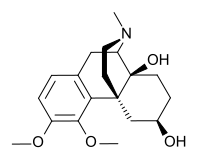

Several semi-synthetic opioids were developed in Germany in the 1910s. The first, oxymorphone, was synthesized from thebaine, an opioid alkaloid in opium poppies, in 1914.[228] Next, Martin Freund and Edmund Speyer developed oxycodone, also from thebaine, at the University of Frankfurt in 1916.[229] In 1920, hydrocodone was prepared by Carl Mannich and Helene Löwenheim, deriving it from codeine. In 1924, hydromorphone was synthesized by adding hydrogen to morphine. Etorphine was synthesized in 1960, from the oripavine in opium poppy straw. Buprenorphine was discovered in 1972.[228]

Opium alkaloids and derivatives

Phenanthrenes naturally occurring in (opium):